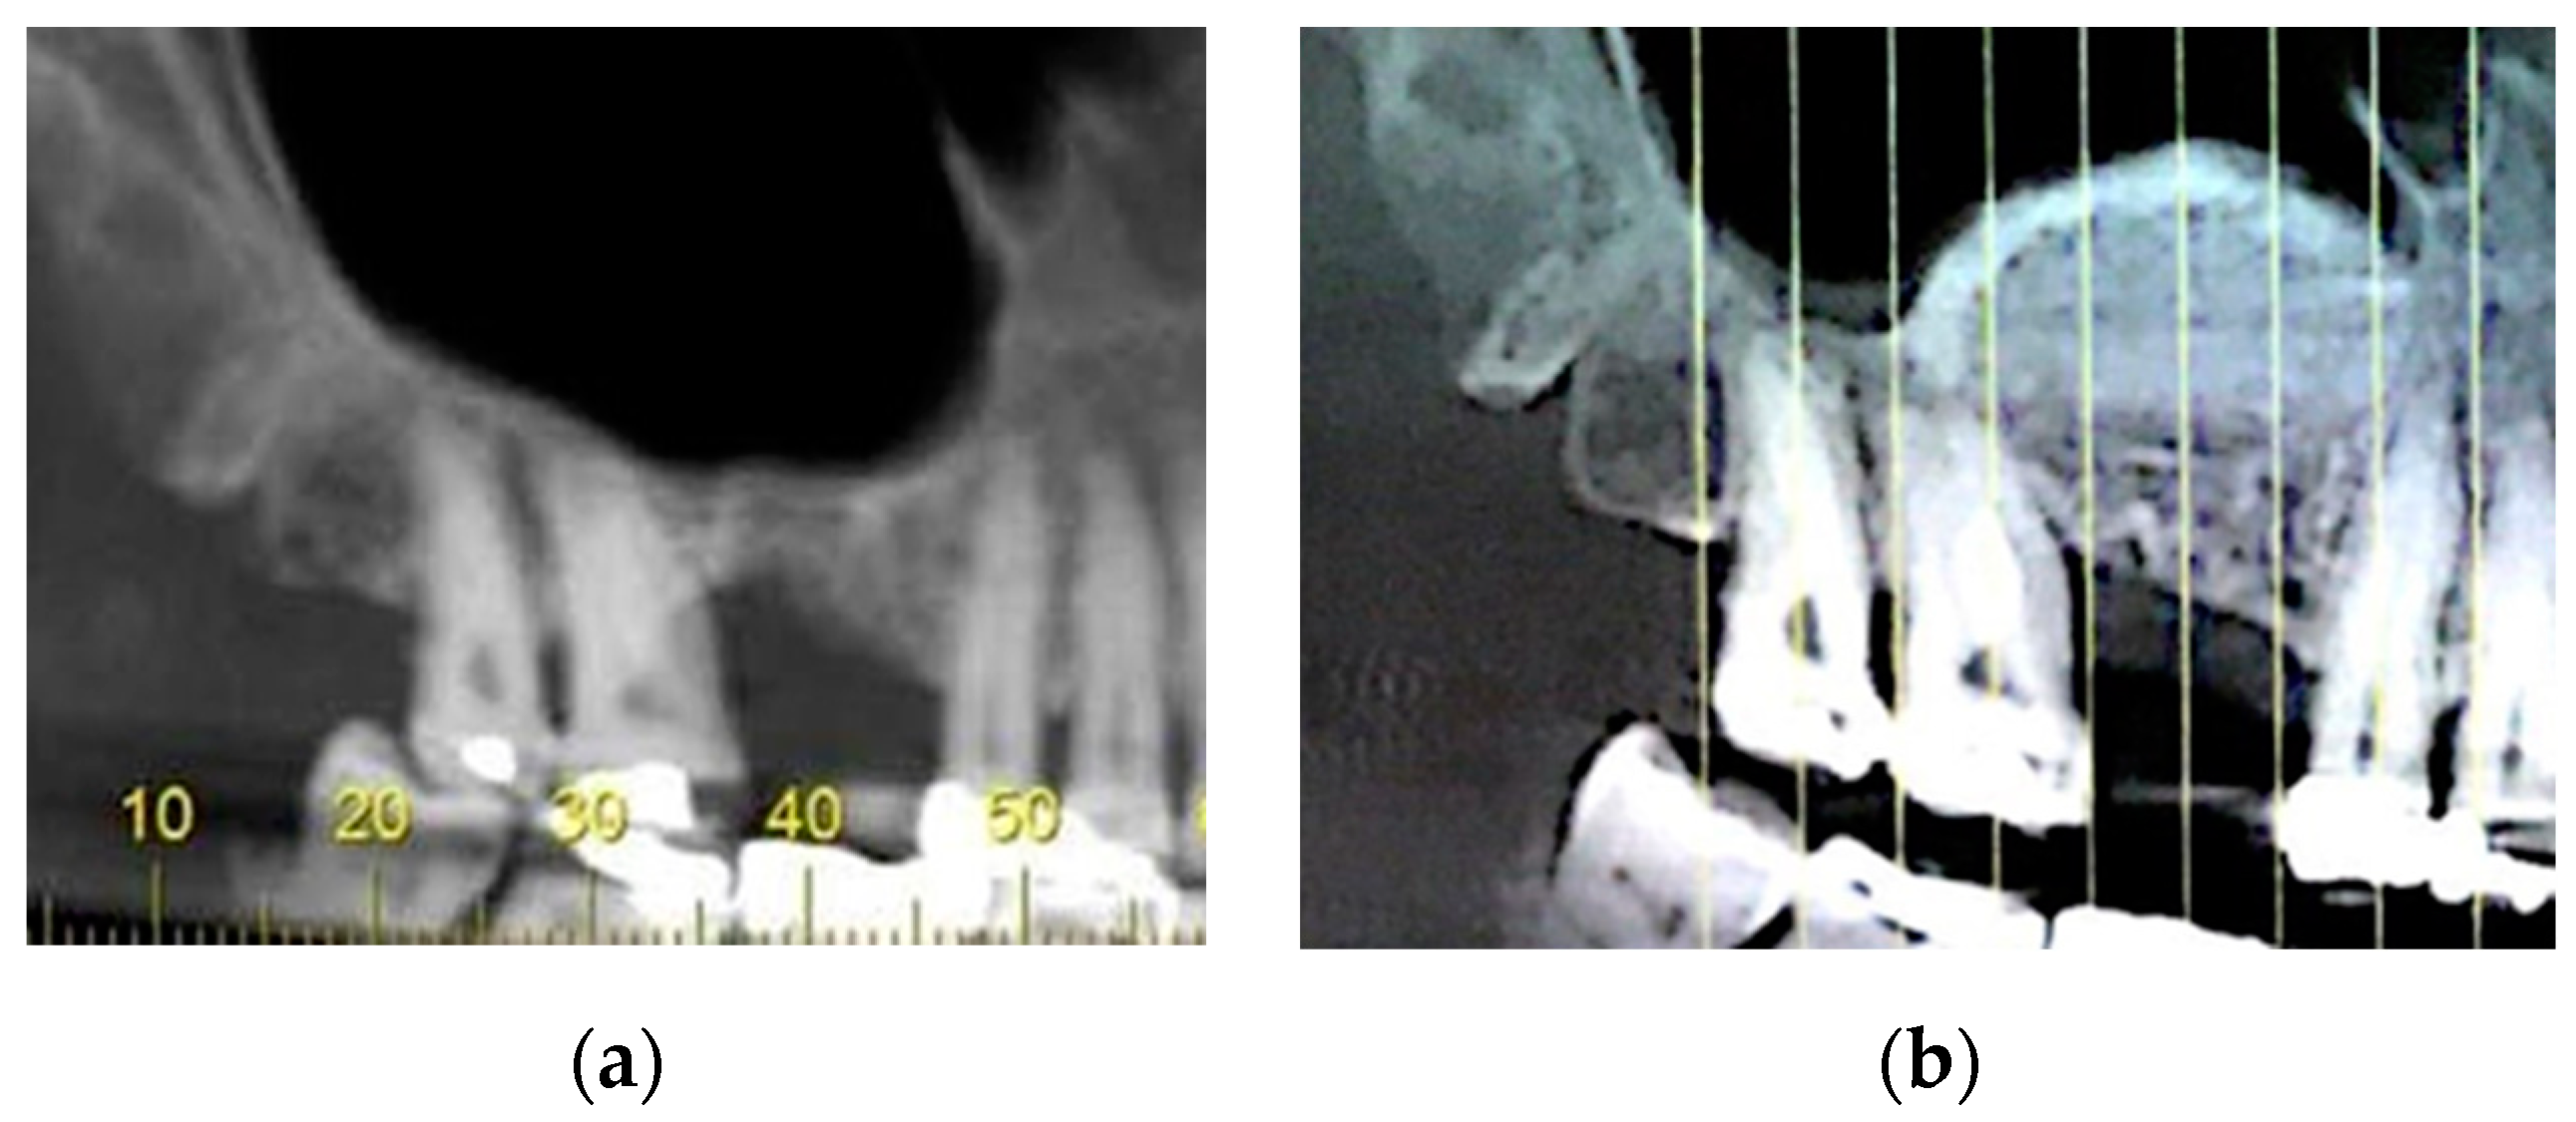

3.1. CBCT Scan Evaluation

3.2. Postoperative Measurements